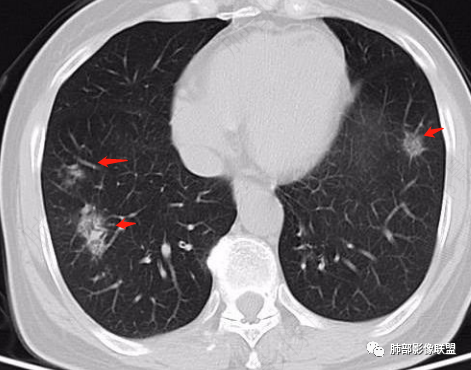

2、CT表现为两肺下叶结节影、斑片影、磨玻璃影,沿支气管血管束分布,部分支气管壁显示增厚。粗略一看部分病灶内似可见“细网格影”,但是仔细观察,可发现此“细网格影”不同于我们常见的“细网格影”,尤其是右肺下叶病灶,可以观察到病灶内部的网格上有高密度结节感或颗粒感,部分层面见“反晕征”,且反晕的边缘亦可观察到结节感。未见胸腔积液。

2、好发部位与其它结核类似,上叶及下叶背段为主。 3、烟花征,反晕征,环呈结节状,可以伴随空洞,树芽征,结节灶,胸水。(反晕征:一般周围实性环形高密度影,中央呈低密度;一般环超过圆的3/4,结核的环主要是小叶核心结节组成,类似于多发树芽征聚集,边缘结节感。中央的晕:可以是腺泡结节,树芽征,细网状,磨玻璃影,很少正常,主要成分是小叶内间质增厚、小叶核心结节、肺泡内病变。)其实也体现了结核的多灶性、多态性特点。

4、其实不一定完全表现为反晕征,还有比较密集的烟花,聚集成团,与反晕征同在。